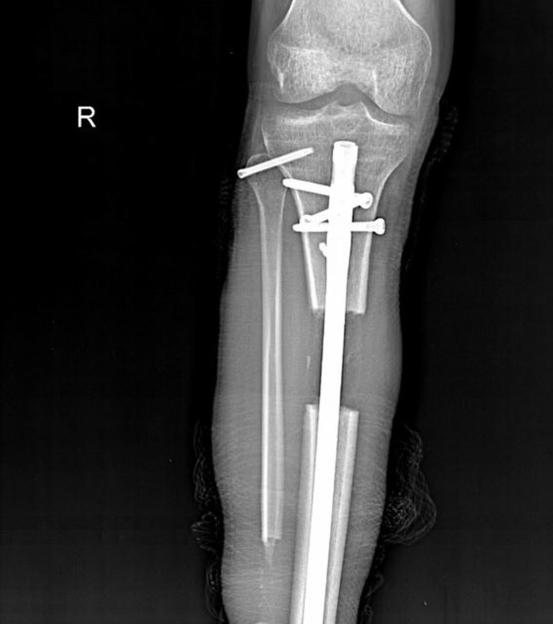

An x-ray of Dynzell Siger’s leg shows a fixator attached to the bone through his skin. A screw was then placed inside the bone in a surgical procedure to lengthen his legCredit: Kennedy News